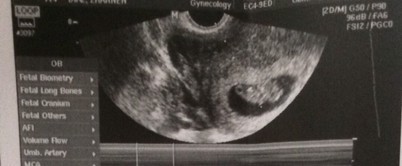

Hi mga mamsh, ilang weeks po kayo nung una nyo nakita si baby sa trans v? On saturday pa po kasi ako nakasched magpatrans v. As per tracker 6weeks & 3days plang po ako nun. May makikita na po kaya baby?? Share nyo naman kwento nyo mga mamsh kung ilang weeks una nagpakita si baby sa trans v. Thanks in advance. #advicepls

Sakin 9weeks and 1day🤰☺️🥰💕

5 weeks sa trans-V nakita na sa akin

6weeks and 2days may heartbeat n rin

6 weeks po may hb na po sya 😇😍

Sa akin 6w2d may heartbeat na🥰

7 weeks po ako . kita naman sya.